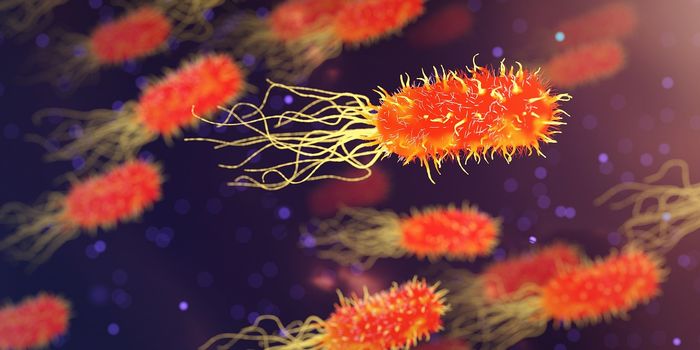

SEP 30, 2016MicrobiologyCurrent hospital laboratory testing is not great at identifying bacterial infections; it can take precious time and reso ...